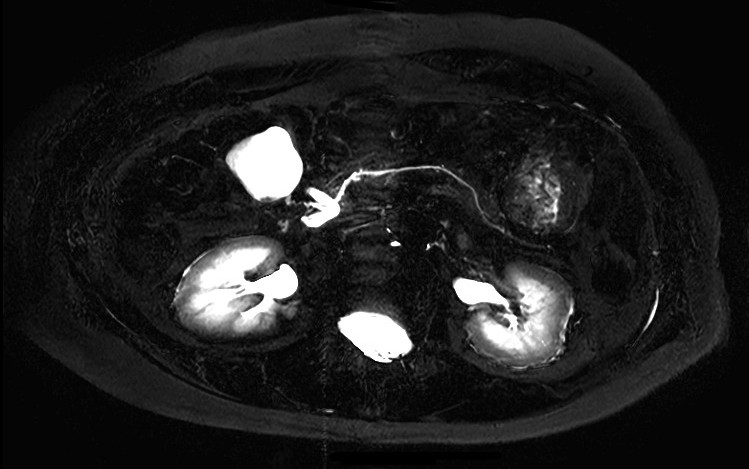

Axial MRCP 2D